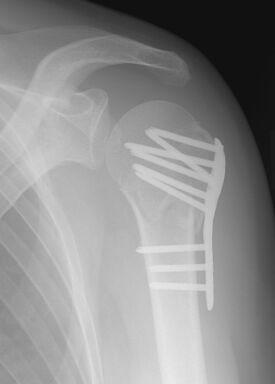

POST-OPERATORIO

POST – OPERATORIO